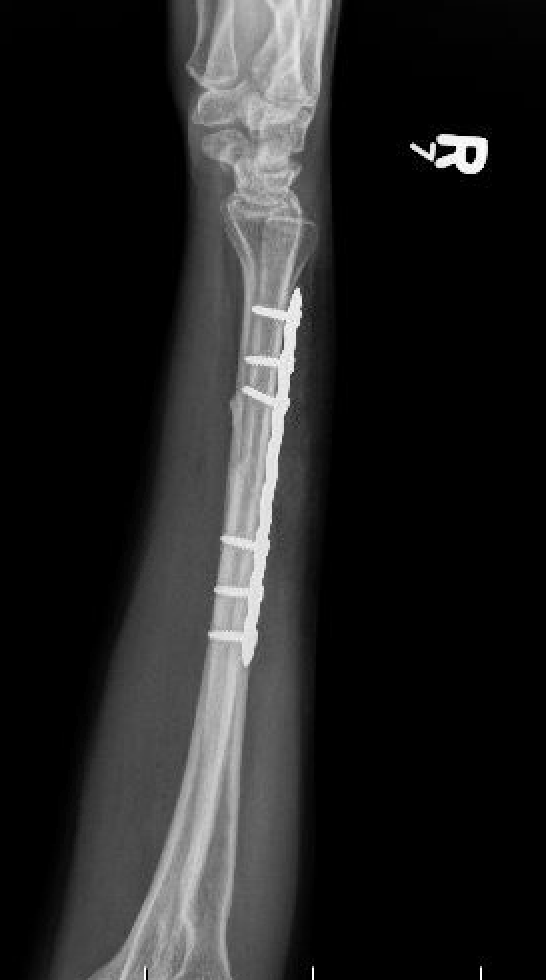

Compression plating

Ulna nonunion after plating

Results

- IM K wire v plate in 54 patients

- 3 nonunions with plate, none with IM wire

- 11% of patients required plate removal